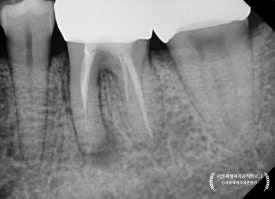

곧이어 치근단엑스레이를 찍어보았지요.

어금니는 뿌리가 여러개기 때문에, 경우에 따라 각도를 달리하여

2장 이상 촬영하기도 한답니다.

통상 아래 어금니에는 신경이 4개 (적으면 3개, 많으면 5개) 있게 마련이죠.

그런데 조금 이상합니다.

4개 중에 2개가 뿌리 전체 길이에 못미치게 치료가 되어 있습니다.